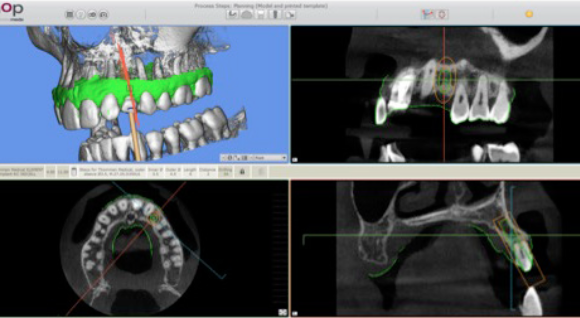

Step 4 — Transfer to SMOP and guide design. With a single click, the entire plan — 3D volume, digital impression, implant position, and references — transferred from CS 3D Imaging to SMOP guided surgery software. No need to reload data, manually align scans, or re-plan the implant position. The SMOP service centre designed the surgical guide and 3D-printed it, shipping it back with a Thommen Medical guided surgery sleeve.

Implant planning data transferred from CS 3D Imaging to SMOP guided surgery software SMOP software displaying the transferred implant plan

Step 4a One-click transfer from CS 3D Imaging to SMOP — no manual re-alignment or re-planning required.

Surgical guide designed in SMOP software Surgical guide design detail in SMOP software

Step 4b Surgical guide designed in SMOP software. The guide only partially covers adjacent teeth — providing full site visibility, better cooling during drilling, and easier instrument access.